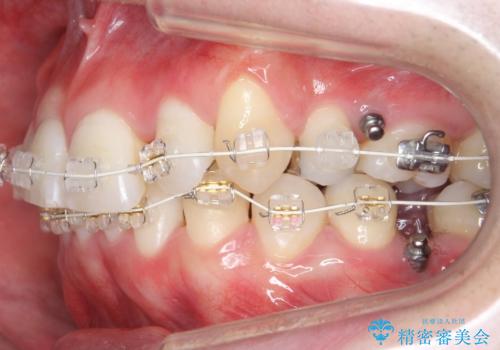

下の歯がないところに、奥歯が倒れこんでいたため、矯正治療で倒れこんだ歯を起こして、インプラントを植立しました。

上顎の小臼歯2本、下顎の親知らずを抜歯しています。

八重歯の移動のため、矯正用ミニスクリューを使用しています。